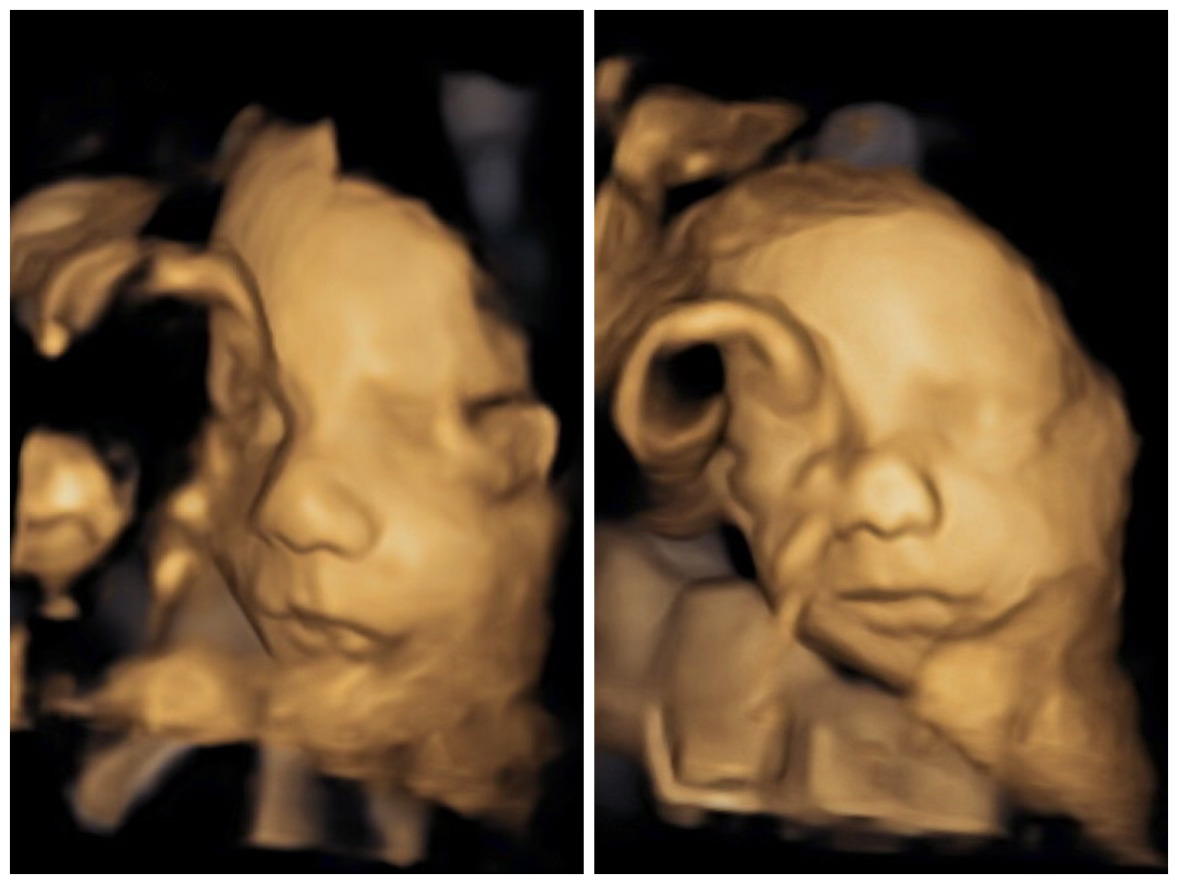

25-week ultrasound (size of Aladdin's magic lamp)

We got to see a 3D image of his beautiful little baby face! (and his umbilical cord!)